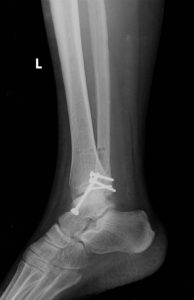

je základní radiologické vyšetření prováděné v ambulantních i lůžkových zařízeních indikované i akutně. Vychází z principu rozdílné absorpce a rozptylu rentgenového záření v jednotlivých tkáních lidského těla ve směru ohnisko – přijímač obrazu. Výsledné zobrazení pak přináší zřetelnou informaci o sledovaných strukturách, kterými jsou skelet, měkké tkáně a struktury s náplní kontrastní látky. Skiagrafický zobrazovací systém umožňuje dosáhnout velkého rozlišení vysokého kontrastu a velkého prostorového rozlišení u zobrazení při možnosti dosažení nízké radiační zátěže pacienta.

Rentgenové vyšetření břicha.Přístrojové vybavení a ukázkové snímky:

- Siemens Multix Fusion, Siemens Ysio Max a Siemens Ysio X.pree